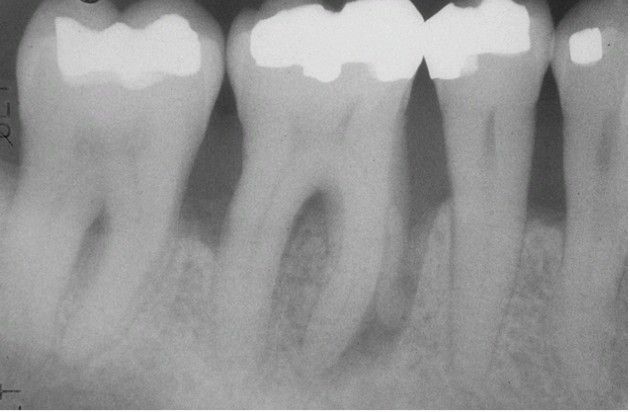

Advanced Adult Periodontitis.

Generalized horizontal bone loss with an isolated vertical defect involving the mesial root of the first mola